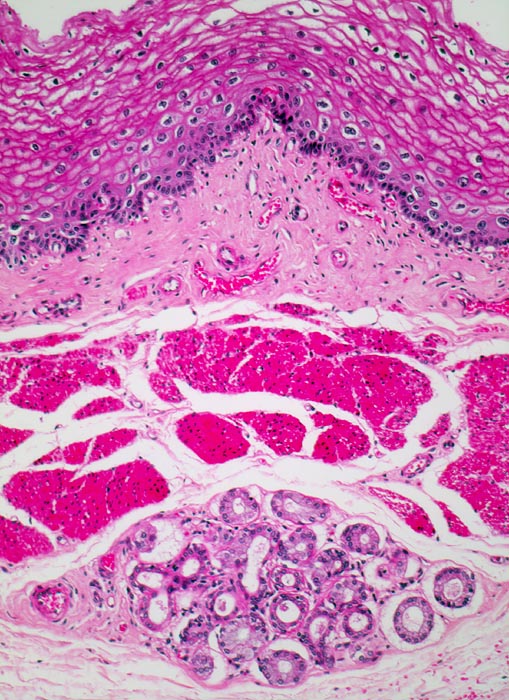

Mikroskopisch zeigen die meisten Plattenepithelkarzinome einen mittleren Differenzierungsgrad und eine wechselnd starke Verhornung. Das fortgeschrittene Karzinom infiltriert angrenzende Strukturen wie den Tracheobronchialbaum, die Aorta und den Nervus recurrens.

• Polypoides exophytisches Karzinom.

• Tumordurchbruch durch die Lamina muscularis mucosae in die Submukosa.

• Der Tumor bildet anastomosierende solide Zellstränge, die fokal im Zentrum verhornen.

• Tumorzellen mit reichlich glasigem eosinophilem Zytoplasma und scharfen Zellgrenzen mit stachelförmigen Interzellularbrücken. Stark vergrösserte, pleomorphe, hyperchromatische Zellkerne mit prominenten Nukleolen.

• Zwischen den Tumorzellsträngen desmoplastisches Stroma mit dichtem gemischtem Entzündungsinfiltrat.